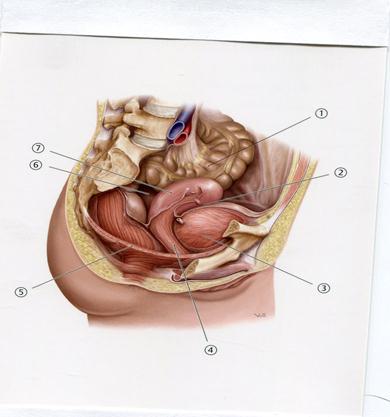

59. Төменде көрсетілген суреттегі белгіленген анатомиялық № 7 құрылымды атаңыз.

+A. Жатыр

B. Жатыр- тік ішек кеңістігі

C. Несеп қуық

D. Тоқ ішек

E. Тік ішек

64. Төменде көрсетілген суреттегі белгіленген № 5 анатомиялық құрылымды атаңыз.

А.Ампуласы

В.Жатыр түтігінің қылтасы

С.Жатыр тесігі

+D.Мойын өзегі

Е.Шашақтары

66. Төменде көрсетілген суреттегі белгіленген №5 анатомиялық құрылымды атаңыз.

А.Жатыр

В.Қасаға симфизі

С.Қынап

+D.Несеп қуық

Е.Тік ішек

82. Әйел адамның шап өзегінің жарығы кезінде, хирург абайсызда жатырдың бекітуші аппаратының бөлігін кесіп алды.Осы операцияны жасау кезінде қандай байламға зақым келді?

А++.Жұмыр

B. Жалпақ

C. Қайырылма

D. Лакунарлы

E. Шап

83.Жатыр мойынымен қынаптың байланысатын аймағында науа тәріздес кеңістік күмбез орналасқан, диагностикалық мақсатта күмбездің қай бөлігі арқылы кіші астау ішастар қуысына пункция жасауға болады?

А.Алдыңғы

B++. Артқы

C. Аралық

D. Оң жақ бүйір

E. Сол жақ бүйір